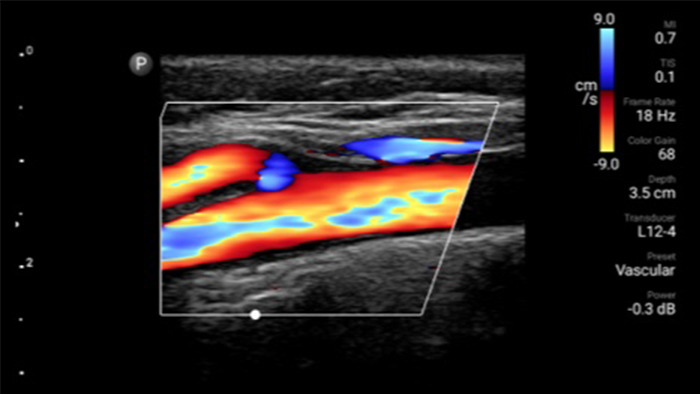

See for yourself Get the full picture with clear whole-body imagery for a fast, accurate response during an emergency.

Lumify transducers for emergency medicine

Lumify L12-4 broadband linear array transducer

• 4 to 1 MHz extended operating frequency range • 2D, color Doppler, M-mode, advanced XRES and multivariate harmonic imaging • High-resolution imaging for abdominal and cardiac applications: Cardiac, OB/GYN, Lung, Abdomen and FAST imaging preset optimizations Lumify aids life-saving technology in prehospital setting

Focused Assessment with Sonography in Trauma (FAST) exam